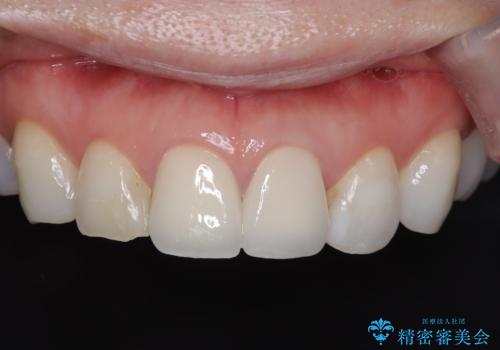

アバットメントは患者様の歯肉に合わせて作製するカスタムアバットメントを入れ被せ物はオールセラミッククラウンで被せています。